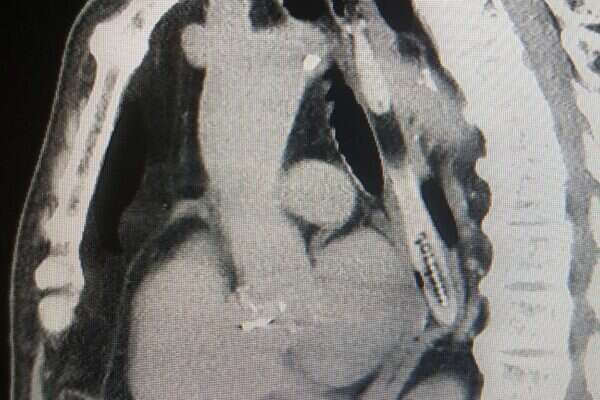

קשיש בן 85 הובא לחדר המיון במרכז הרפואי לגליל בנהריה וסיפר לצוות המטפל כי בלע מברשת שיניים בעת שעסק בניקיון שאריות מזון שנותרו בין שיניו. ד"ר רונית בר חיים, ממחלקה כירורגיה ב' שטיפלה בו בחדר המיון, הורתה על ביצוע בדיקת סי.טי דחופה, בה ניתן היה להבחין בגוף זר שהתברר כמברשת השיניים.

הגוף הזר היה תקוע בתוך לועו של הקשיש ולא ניתן היה להבחין בה עד לביצוע פעולות דימות רפואיות.

הדמייה בה ניתן לראות את מברשת השיניים